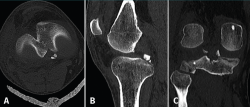

The computed tomography (CT) study evidenced a fracture of the posterior region of the internal tibial plateau with millimetric collapse and sub-centimetre avulsed fragments located immediately medial to the posterior cruciate ligament (PCL), together with a small fracture in the posterior cortical layer of the external tibial plateau without collapse, displacement or comminution (Figure 2).

Figure 2. The axial (A), sagittal (B) and coronal (C) computed tomography views show the avulsed bone fragments dependent upon the posterior root of the medial meniscus, near the insertion of the posterior cruciate ligament.